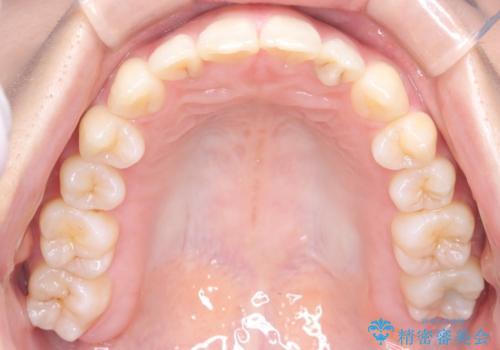

【インビザライン】前歯の凸凹を治したい

- 前歯の凸凹を主訴に来院されました。

インビザラインにて臼歯部の遠心移動を行いながら、できるだけ前歯が出ないように気を付けて治療を行っています。

遠心移動を行う必要があったので、患者様には顎間ゴムを使用していただきました。